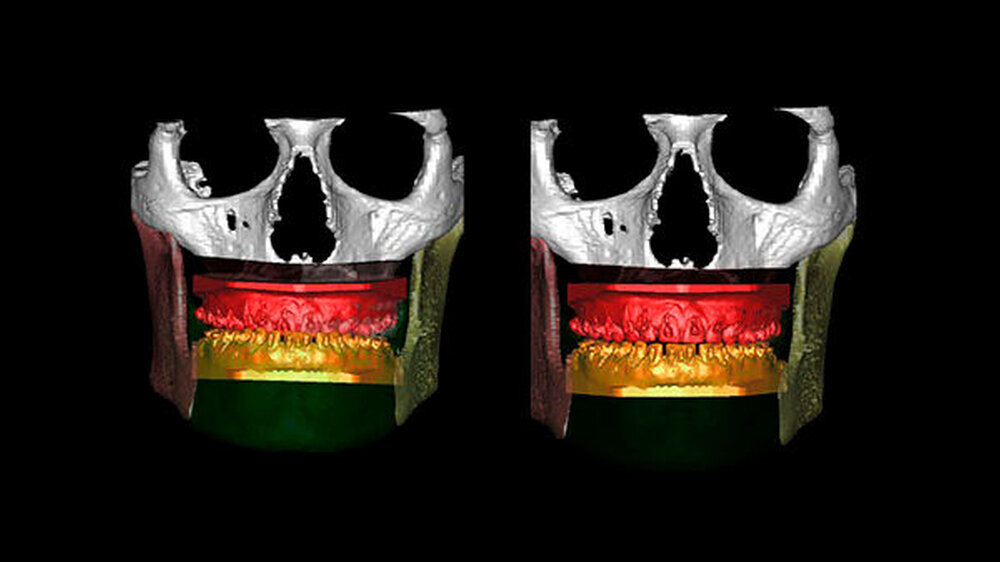

Die Abbildungen 1 und 2 zeigen die klinische Situation bei Erstvorstellung: Der Unterkiefer ist zu prominent. Der Oberkiefer und das Mittelgesicht liegen zurück. In der Front liegt ein umgekehrter Überbiss vor. Der Unterkiefer steht vor dem Oberkiefer. Das erschwert das Abbeißen und Kauen der Nahrung. Die Scans (siehe Abbildungen) dokumentieren, wie aufwendig die virtuelle Operationsplanung erfolgen musste.

Im Dezember 2014 führen die MKG-Chirurgen des Stuttgarter Katharinenhospitals die Umstellung des Ober- und Unterkiefers nach virtueller Chirurgie-Planung durch: Dabei trennen sie den Oberkiefer horizontal vom Gesichtsschädel ab (horizontale Osteotomie in der LeFort Ebene).

Nun muss die Biss-Situation anhand des Computer gefertigten Biss-Schlüssels exakt eingestellt werden, bevor mit zwei Millimeter dicken Osteosyntheseplatten aus Titan der Knochen in der neuen Position mit Hilfe von Titanschrauben fixiert wird. Im Unterkiefer erfolgt die Schnittführung im Zahnfleisch hinter dem letzten Backenzahn beidseits. Nun wird der Unterkiefer mit spezieller Technik durchtrennt. Dies erlaubt eine Verschiebung der Zahn tragenden Basis vom Gelenk tragenden Knochenabschnitt des Unterkiefers.